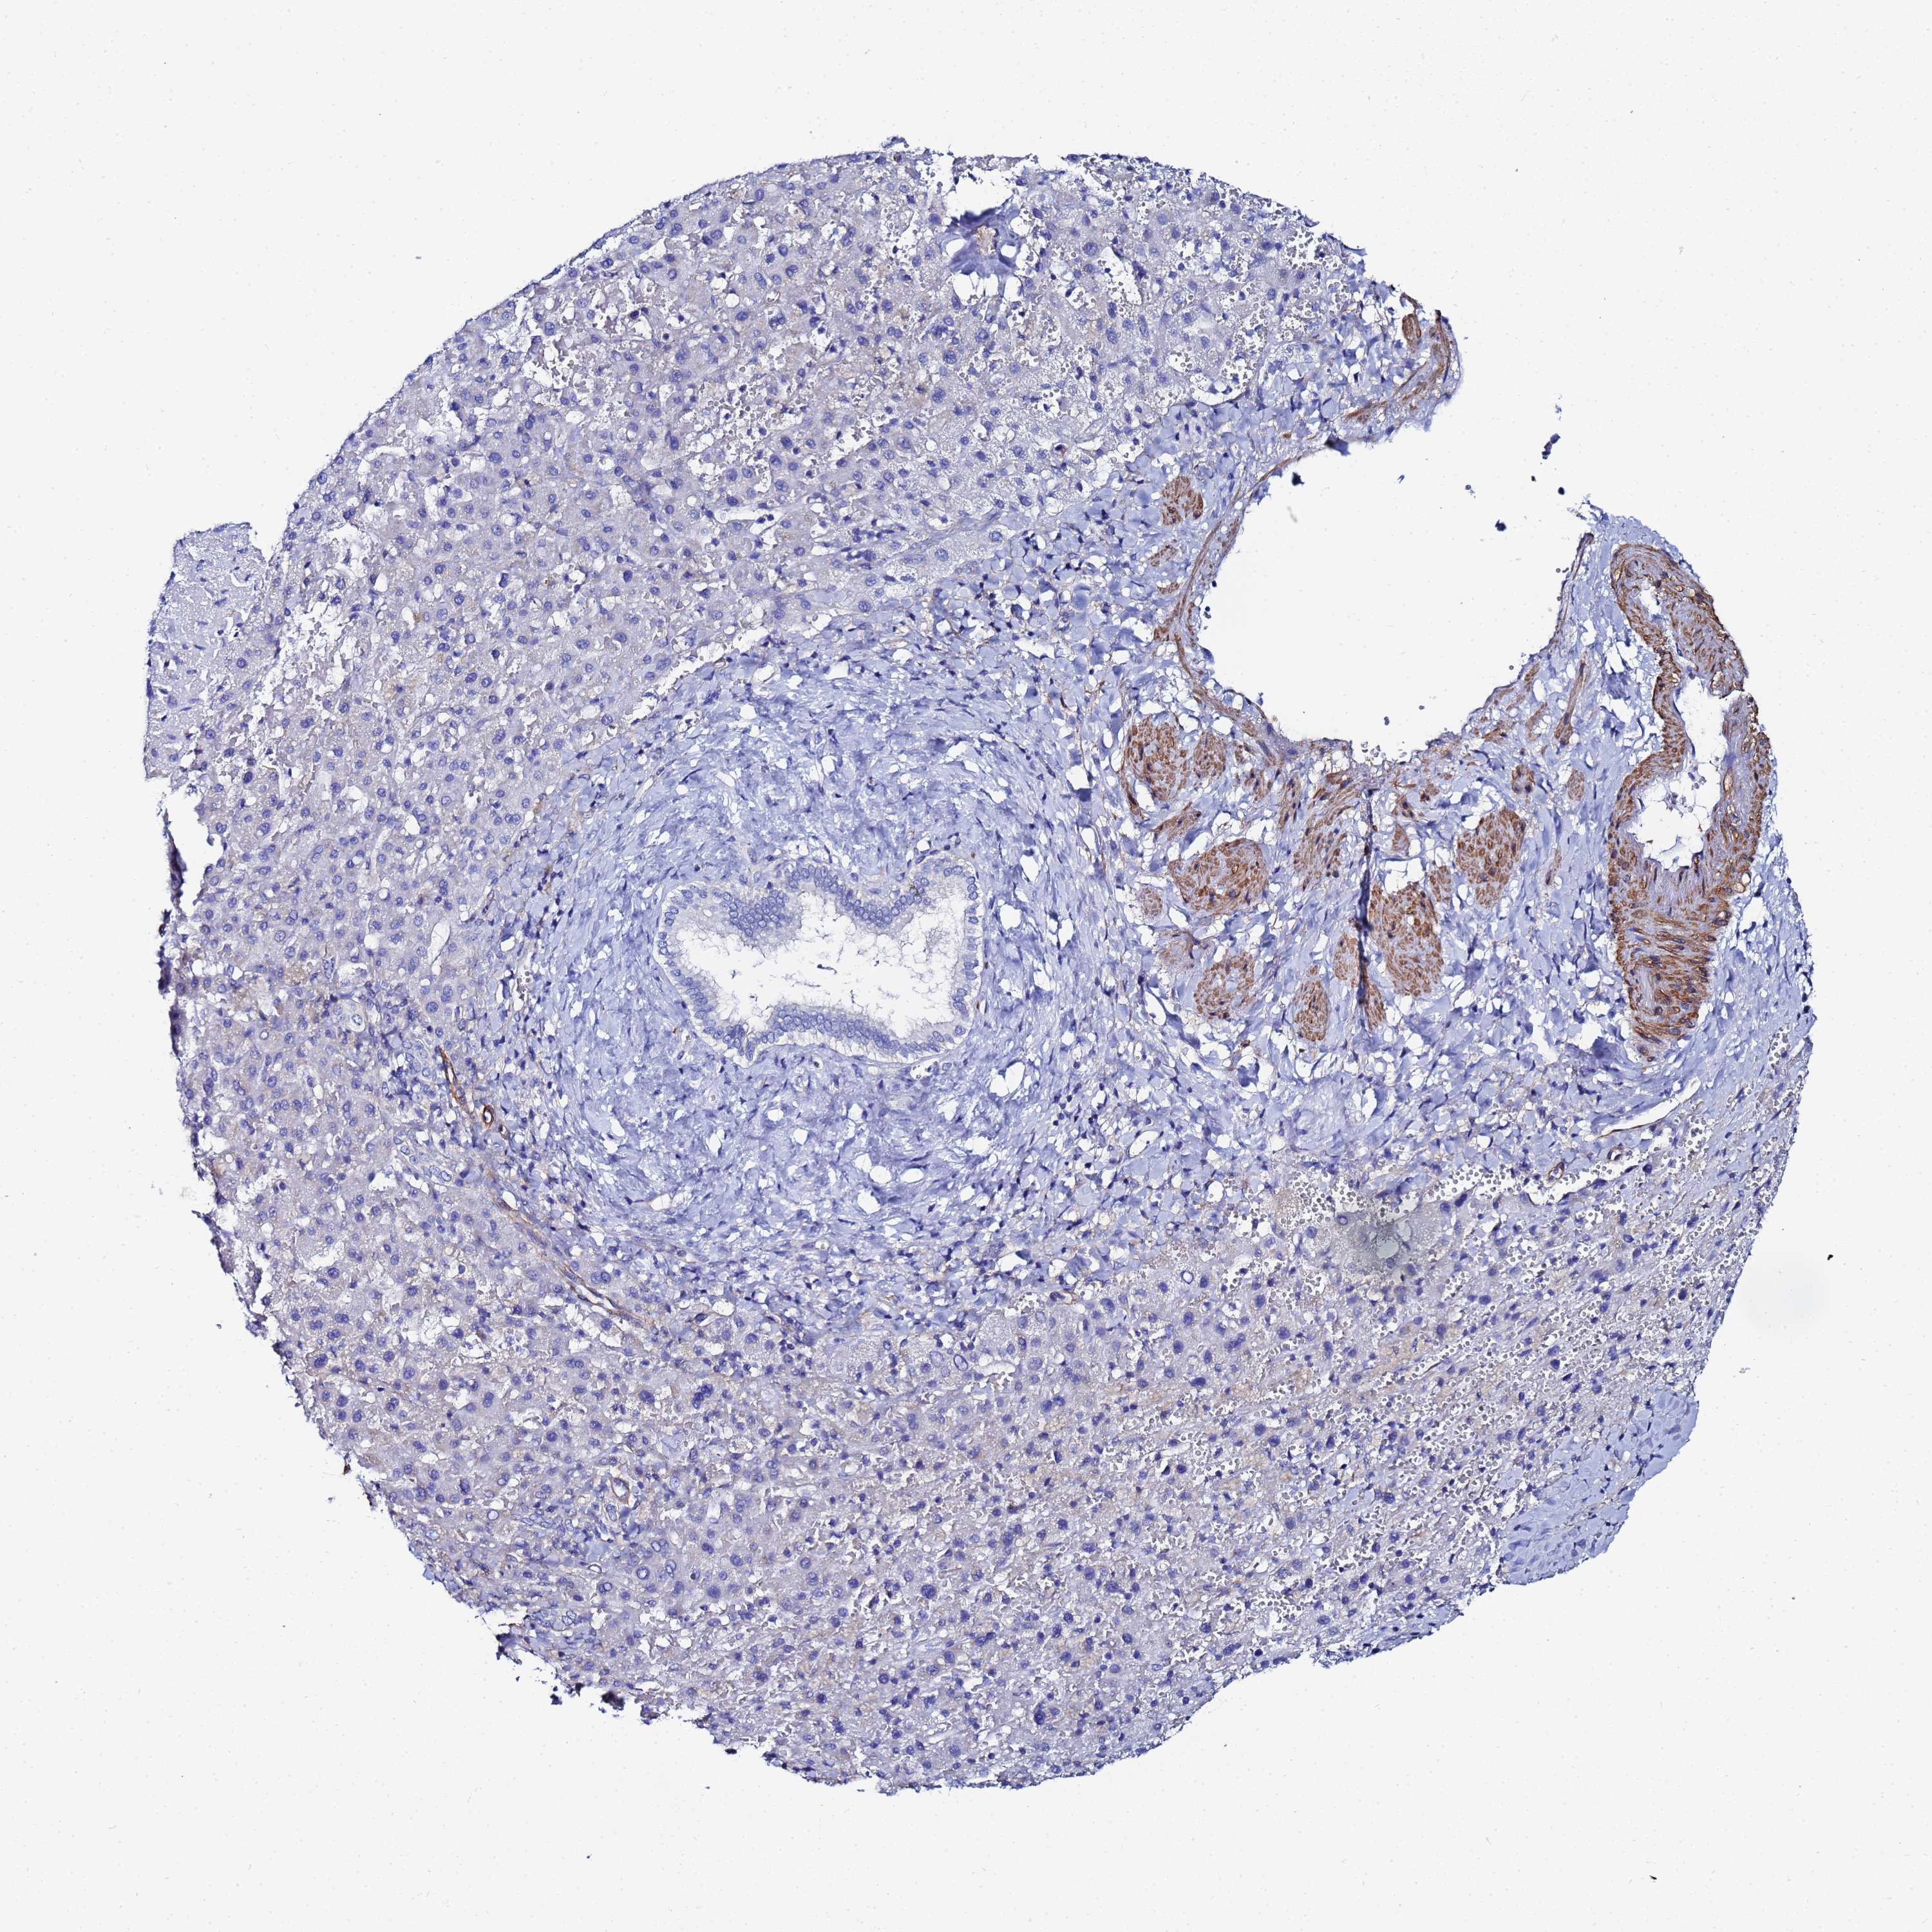

LIVER CANCER - Protein expressioni

A mouse-over function shows sample information and annotation data. Click on an image to view it in a full screen mode. Samples can be filtered based on level of antibody staining by selecting one or several of the following categories: high, medium, low and not detected. The assay and annotation is described here.

Note that samples used for immunohistochemistry by the Human Protein Atlas do not correspond to samples in the TCGA dataset.

Antibody stainingi

Antibody staining in the annotated cell types in the current human tissue is reported as not detected, low, medium, or high, based on conventional immunohistochemistry profiling in selected tissues. This score is based on the combination of the staining intensity and fraction of stained cells.

Each image is clickable and will lead to virtual microscopy that enables deeper exploration of all samples and also displays staining intensity scores, fraction scores and subcellular localization as well as patient and tissue information for each sample.

Antibody HPA001114

Antibody HPA042505

Staining

High

Medium

Low

Not detected

Intensity

Strong

Moderate

Weak

Negative

Quantity

>75%

75%-25%

<25%

None

Location

Nuclear

Cytoplasmic/membranous

Cytoplasmic/membranous,nuclear

Carcinoma, Hepatocellular, NOS

Cholangiocarcinoma